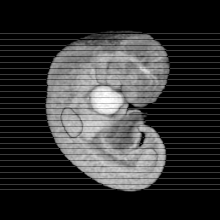

Carnegie Stage 14 (32 post-ovulatory days)

Most embryos at stage 14 are approximately 32 postovulatory days old and measure 5-7 mm in length. Distinguishing criteria for this stage include an open lens pit with invagination of the lens disc and elongated and tapering upper limb buds. The otic vesicle with a well-defined endolymphatic appendage is also a hallmark of this stage.